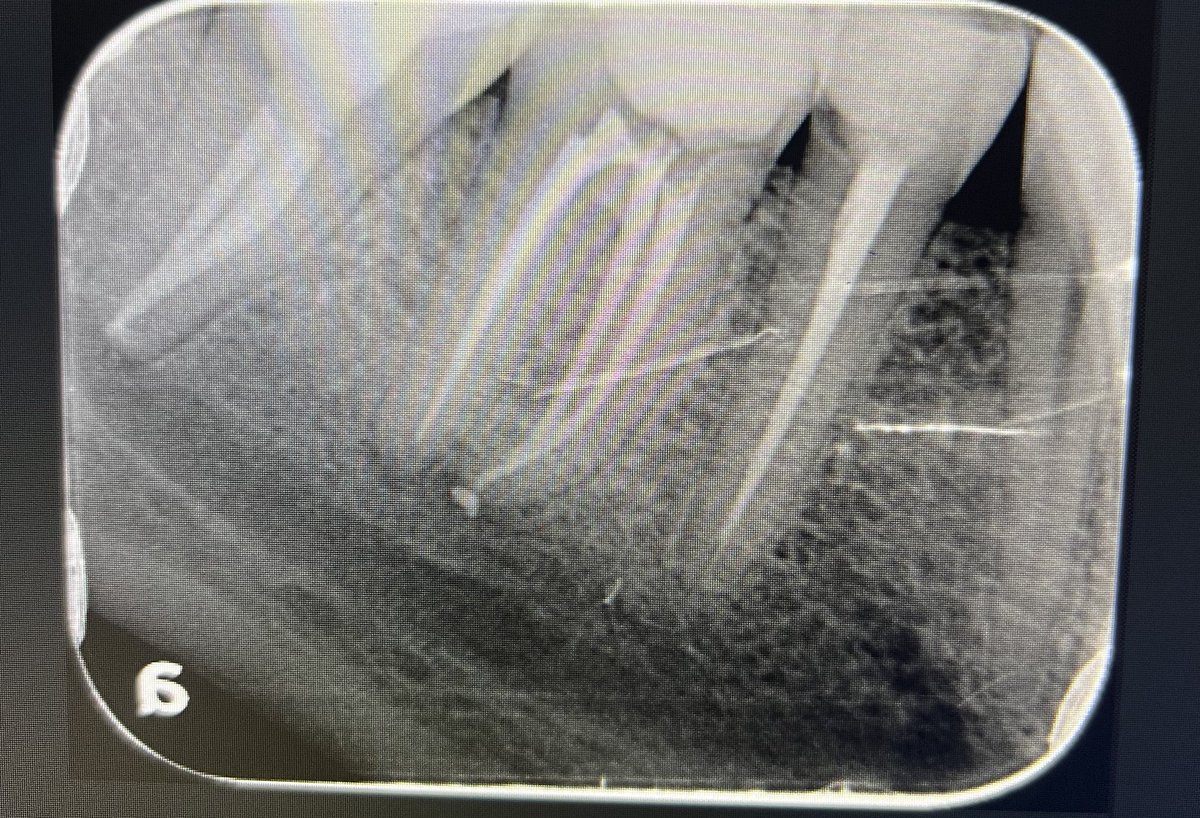

حالة جميلة لصباح اليوم 🙏🏻

Root Canal Treatment #34

Dx:SIP+SAP

Gingival overgrowth and deep caries in the distal wall, Rebuild the distal wall to achieve optimum isolation ✨

Next Step: Crown

#Endodontics